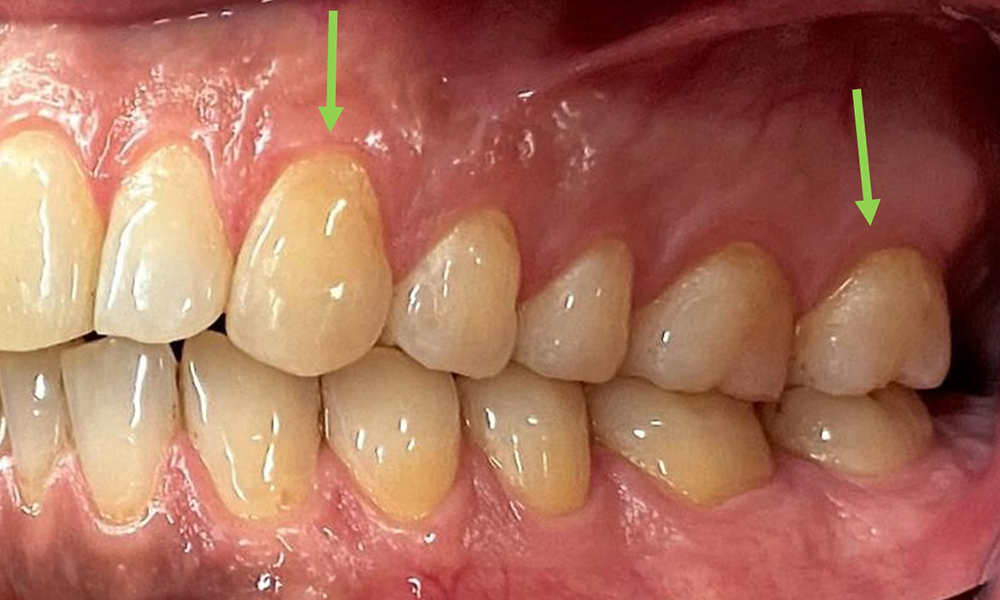

At 1 to 3 mm, the clinical probing depths were within the physiological range. Maxillary recessions of up to 1 mm were observed from 13 to 16 and 23 to 27. The BOP was 15%.

Due to the otherwise favourable general medical condition, the needs determined during the intraoral examination will be decisive for their treatment. It will be essential to periodically determine the probing depths. Gingival bleeding decreases in smokers, which is why the clinical diagnosis of periodontitis can only be made by probing (Fig. 7). Placing exclusive focus on the determination of bleeding indices may obscure existing periodontitis or gingivitis. (5)